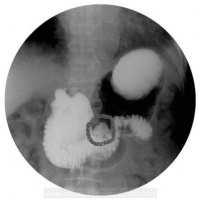

1.X线钡餐检查:可发现十二指肠憩室表现为突出于肠壁的袋状龛影,轮廓整齐清晰,边缘光滑。加压后可见龛影中有黏膜纹理延续到十二指肠,有的龛影在钡剂排空后,见到为憩室腔内残留的钡剂阴影较大的憩室,颈部较宽,在憩室内有时可见气液面。当憩室周围肠黏膜皱襞增粗,轮廓不整齐,局部有激惹征象或憩室排空延长,或有限局性压痛,认为是憩室炎的表现,如憩室固定不能移动,是有憩室周围炎的表现。

继发性十二指肠憩室常伴有十二指肠球部不规则变形并有肠管增宽阴影。当憩室较小或颈部狭窄,其开口部常被肠黏膜皱襞掩盖,或憩室内充满大量食物残渣,而不易发现憩室的存在,

如有少量钡剂进入憩室或可见一完整或不完整的环影。用低张十二指肠X线钡剂造影可增加憩室的发现率。